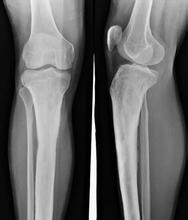

根据慢性病史、临床表现和X线所见,诊断比较容易。必要时可做关节滑液检查,以证实诊断。X线改变不能说明是原发性骨关节病,应从病史中明确病损是原发性或继发性。 》》》百看不如一问,咨询专家如何对症治疗